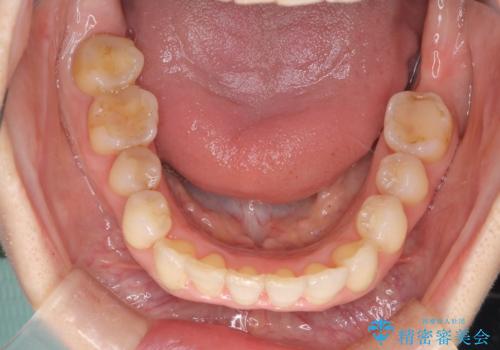

今回の治療では、右上5番の抜歯スペースを活用して八重歯(3番)を後方へ誘導しました。

インビザライン独自の3Dシミュレーションに基づき、必要な歯だけをピンポイントで動かすことで、抜歯を伴う大きな移動も効率的に行いました。

治療の結果、突出していた八重歯はきれいなアーチに収まり、左右対称でバランスの取れた口元になりました。インビザラインは自由に取り外しができるため、治療期間中も口腔内を清潔に保ちやすく、患者様もストレスなく治療を完了されました。